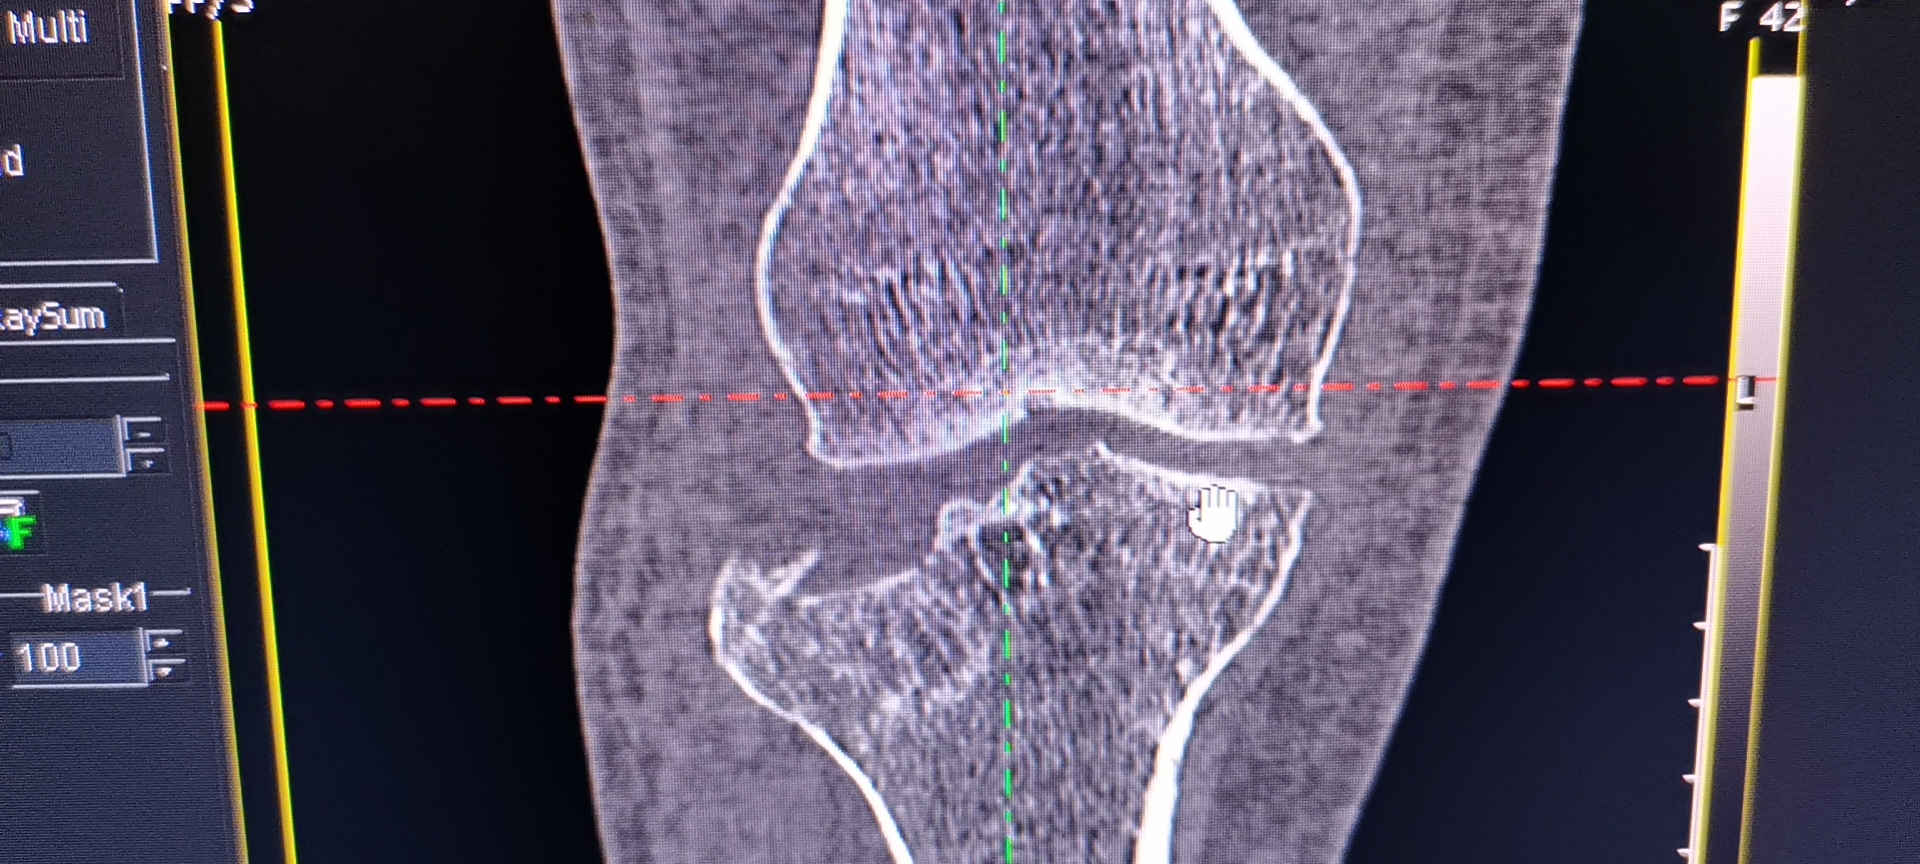

- X线片:首选初步检查,拍摄膝关节正侧位片,可明确骨折是否存在、大致移位方向,但难以显示关节面细节及软组织损伤。

- CT(计算机断层扫描):必查项目,通过三维重建可清晰显示关节面塌陷程度、骨折块数量及移位情况,为分型和手术方案制定提供关键依据。